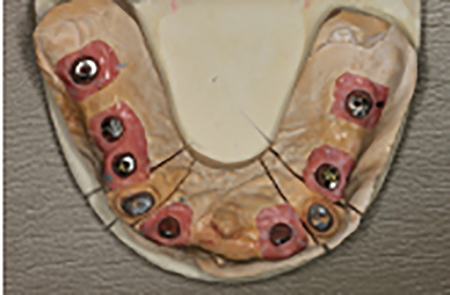

The final treatment plan would require implants in the #16, 14, 12, 22, 24 and 26 positions. The fixed provisional prosthesis would make use of provisional abutments on #17 and 27, 13, 23 and 11. The plan would involve serial extractions and grafting procedures to preserve bone volume in the ideal sites while avoiding any load on the newly grafted sites using strategic teeth to serve as provisional abutments. Patient accepted this solution and agreed to keep teeth #13 and #23. Benefits include cuspid rise occlusion, bone preservation and proprioception (also to minimize the significant risk with adjacent implants in the anterior zone).

- N.B. Existing #17 to be converted to #16, existing #16 to be converted to #15 and 14, existing #26 to be converted to #24 and 25. Lastly #27 will be converted to 26.

- Immediate implant placement in sites #12, 22, 14 and 24.

Abutment try-in